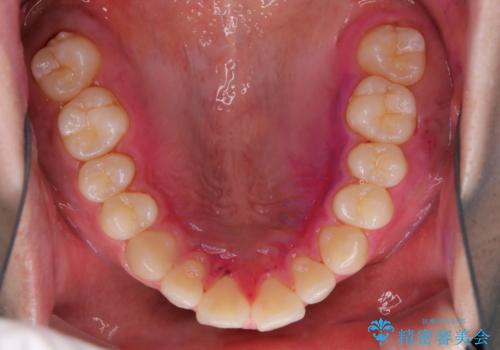

親知らずを抜いて1週間後にPMTC 歯のクリーニング

- 親知らずの抜歯後の約1週間後に抜糸(縫った部分の糸とり)で来院されました。その際、抜歯後は傷口が怖くて歯磨きが上手くできず、汚れや口臭が気になるためクリーニングも希望されました。

抜歯後は多少出血したり、違和感や痛みを感じたりすることがあります。そのため親知らずを抜いたり、外科的な処置をするといつも通りの歯磨きがしづらくなります。また、傷口の周りが心配で、歯ブラシをするのが怖くなるものです。抜歯後落ち着いたら、歯科医院にて専門の機械を使用しクリーニングをすることがおすすめです。抜歯前や後にPMTCを行うことで、お口の中の健康維持につながり、その後の感染・腫れ・口臭予防などになります。

親知らず抜歯後正常に治癒が進んでいれば1週間後から可能です。